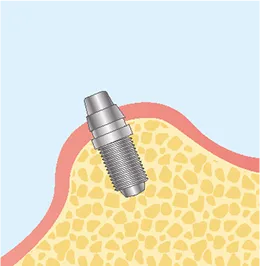

FLOW02

二次オペ

(アバットメントの装着)-

STEP3

アバットメント埋入

STEP4

縫合

FLOW03

上部構造

(人工歯)の装着最終的な被せ物(上部構造)を製作・装着します。